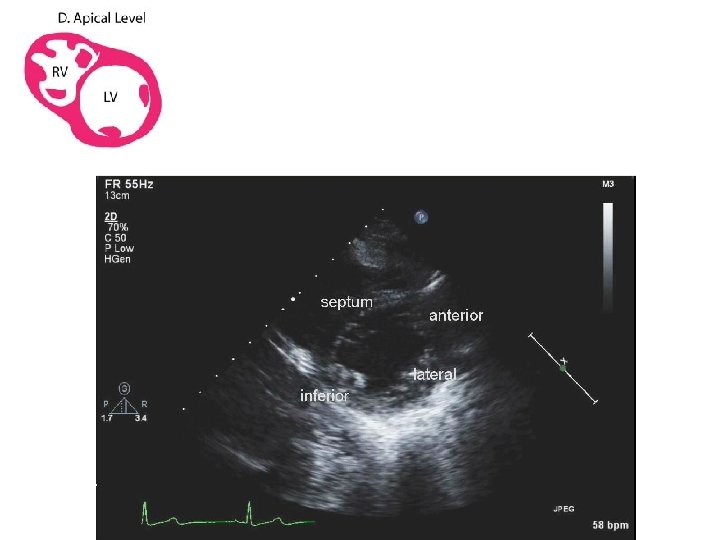

APICAL 4 CHAMBER VIEW

SUBCOSTAL SHORT AXIS